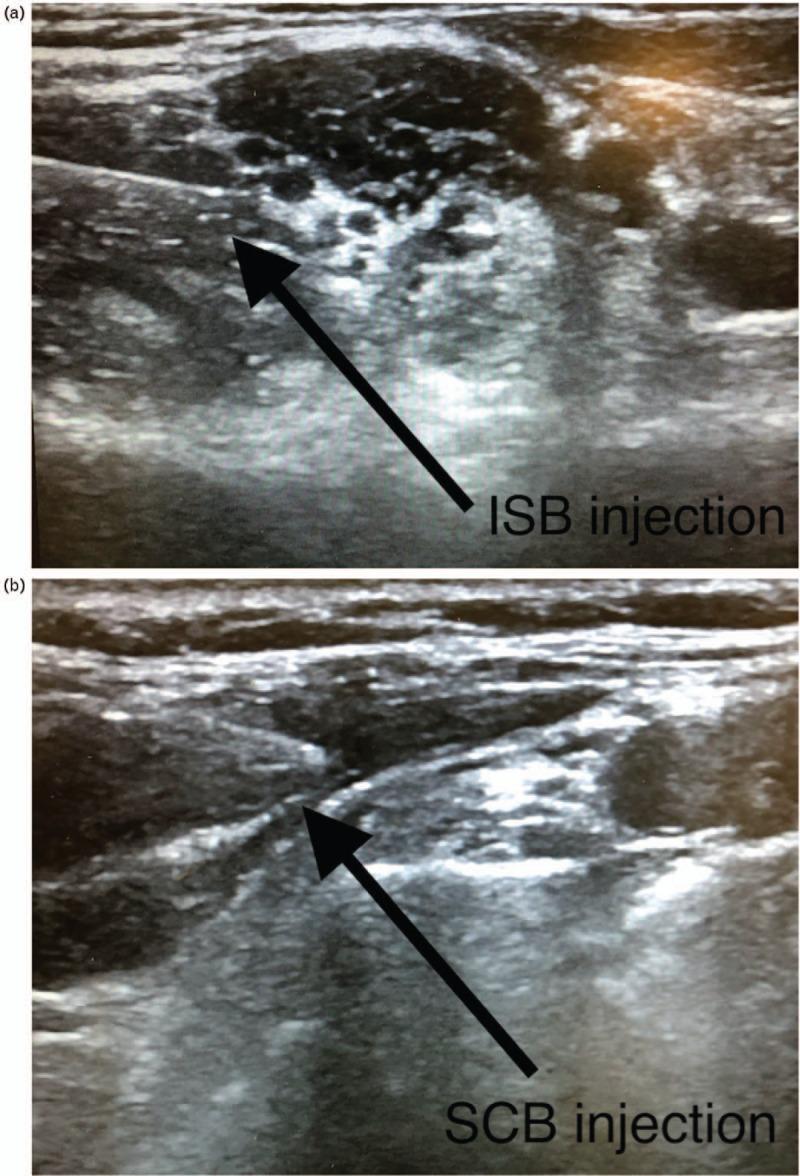

Ultrasound-guided interscalene block (ISB) is the reference technique for pain control after ambulatory upper limb surgery, but supraclavicular block (SCB) is an alternative.

The aim of this study was to compare the efficacy of SCB vs. ISB in patients undergoing ambulatory arthroscopic rotator cuff repair (ARCR), with the hypothesis of noninferiority of SCB analgesia compared with ISB.

Patients were randomly allocated (1 : 1) to receive a single injection SCB or ISB, as well as general anaesthesia. All patients received a postoperative analgesic prescription for home use before leaving hospital (including fast-acting oral morphine sulphate). Patients completed a telephone questionnaire on days 1 and 2 postsurgery.